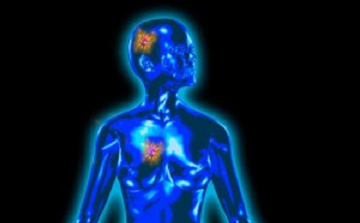

Új védőfegyver vírusok ellen

Vírusok elleni, eddig csak növények és gerinctelenek esetében ismert védőfegyverre bukkantak emlős állatoknál kutatók.

Kutatók sikeresen hallgatták le az agyhullámokat

A Stanford Egyetem kutatói rohamok során jelentkező agyi aktivitást konvertáltak zenévé.

Baktérium is okozhatja a legveszélyesebb rákot

Lenyűgöző felfedezés a rák valódi okáról

Meggyógyulhat a beteg, ha megérti betegsége okát.